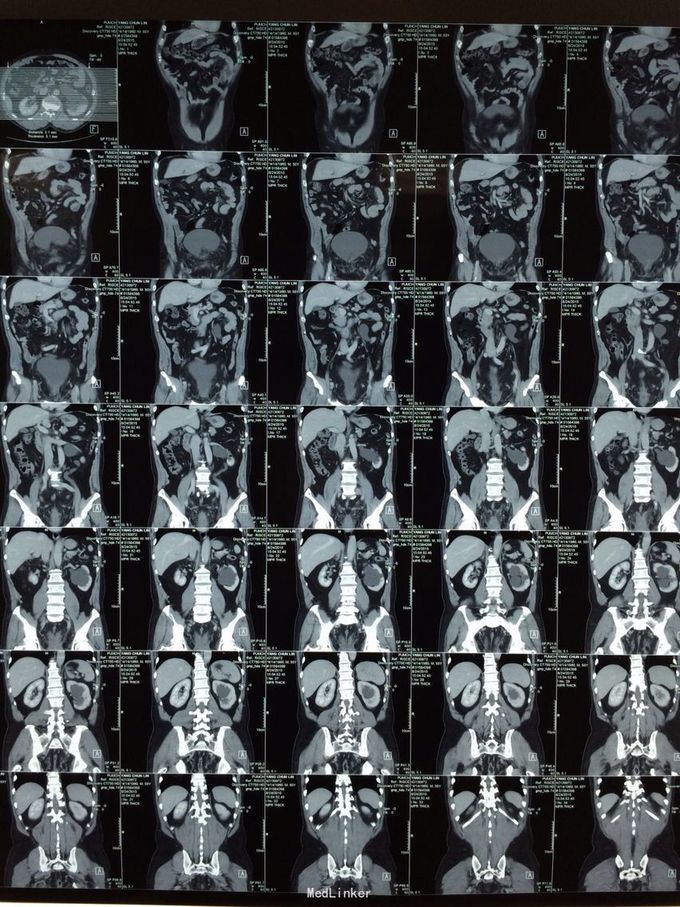

体检发现左肾积水3月余。无尿频尿急,排尿困难。当地医院彩超示:1双肾积水2右输尿管扩张3左侧输尿管走形迂曲并扩张4膀胱位置抬高5前列腺显示不清。为求进一步治疗前来我院。门诊行检查后诊断为盆腔脂肪增多症,建议患者行左肾造瘘。患者表示拒绝,至北京某医院就诊,给予行双侧输尿管D-j管置入,未成功。再次至我院就诊,门诊以“盆腔脂肪增多症”收住院。

盆腔脂肪增多症诊断目前没有统一标准,目前比较公认的是:CT,MRI发现盆腔脂肪异常增多;膀胱受压变形呈梨形、泪滴状或香蕉状;腺性膀胱炎表现;直肠-乙状结肠明显受压拉直,结肠袋消失;合并肾积水. 满足以上1或+ 2-5任意一条即可诊断;个人认为MRI提供的参考信息大于CT。输尿管D-J置入往往因输尿管受压迂曲而失败,无法缓解病情。输尿管皮肤造瘘或肾造瘘也许是这些患者的最终结局,高位的回肠代膀胱也是一种选择但存在肾积水缓解不好的风险。需要特别指出盆腔脂肪剃除不可取。长期来看输尿管膀胱再植也是无效的。